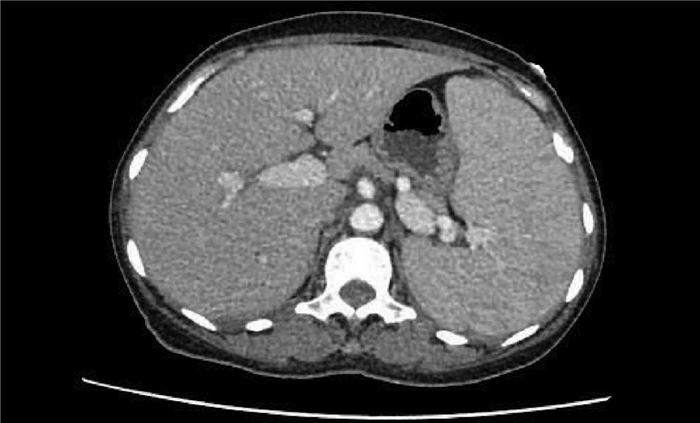

Construction of a new patient-derived xenograft model of human liver cancer in mice with normal immunity

Huixin TANG, Shanshan LI, Feng HONG, Yanzhen BI, Quanyi WANG, Xiaobei ZHANG, Shumin CHENG, Zhongping DUAN, Zhenfeng SHU, Yu CHEN

2021, 37(11): 2584-2588. DOI: 10.3969/j.issn.1001-5256.2021.11.019

Abstract(2475) HTML (633) PDF (3030KB)(178)

Abstract:

Objective  To establish a new patient-derived xenograft (PDX) model of human liver cancer by inoculating the complex of human primary liver cancer cells and a novel microcarrier (microcarrier 6) into mice with normal immune function.  Methods  Primary liver cancer cells were isolated and extracted from the fresh human liver cancer tissue of five patients and were then co-cultured with microcarrier 6 to construct a three-dimensional tumor cell culture model in vitro. According to the type of graft, 75 male C57BL/6 mice were divided into cell control group, microcarrier control group, and experimental group (each sample corresponded to three groups, with 15 groups in total and 5 mice in each group). The liver cancer cell-microcarrier complex was implanted into the mice by subcutaneous inoculation, and tumor formation time, tumor formation rate, and histopathological manifestations were observed. The Fisher's exact test was used for comparison of categorical data between two groups.  Results  As for the liver cancer cells from the five patients, tumor formation was observed in the mice corresponding to three patients. In these three experiments, tumor formation was not observed in the control groups and was only observed in the experimental groups, and 12 of the 15 mice in the experimental groups had successful tumor formation, with a tumor formation rate as high as 80%, which was significantly different from that in the cell control groups and the microcarrier control groups (all P < 0.05). The tumor formation time was 5-7 days; the xenograft tumor grew rapidly, and HE staining showed nested or flaky cells with obvious heteromorphism, with the presence of pathological mitosis; immunohistochemical staining showed positive CK8/18, Hep, and Gpc-3, which was in accordance with the characteristics of human liver cancer cells.  Conclusion  This experiment successfully establishes a new PDX model of human liver cancer based on the complex of microcarrier 6 and human primary liver cancer cells in mice with normal immunity. This model can be used to better elucidate the mechanism of the development and progression of liver cancer in the body with normal immunity, and besides, it also provides a new animal model with higher value for the precise treatment of liver cancer.